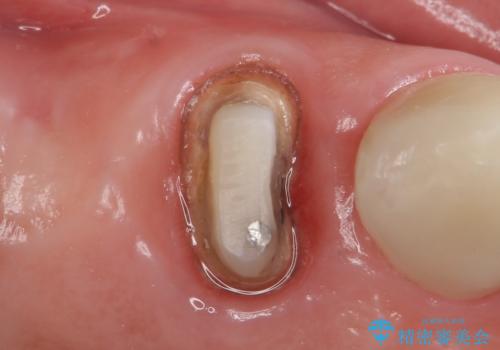

- アメリカの歯科医院にて治療途中の歯の仮歯が割れてしまったので診て欲しいといらっしゃった方の症例です。

しばらくアメリカに戻れそうにないため、当院での治療を希望。土台の築造まで処置は終わっているとのことだったのでオールセラミッククラウンによる補綴のみを行いました。